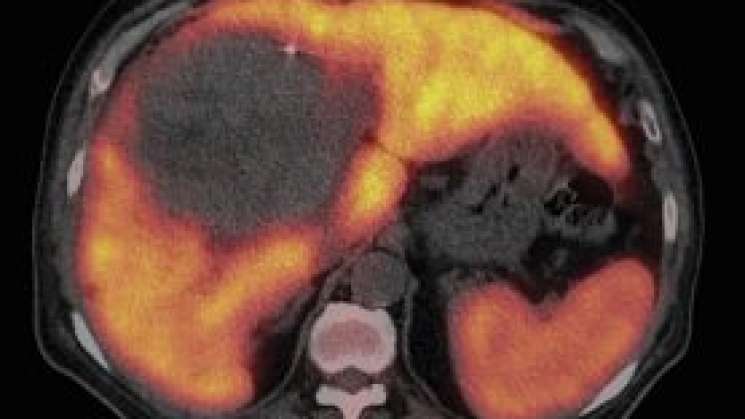

FOTO: Radioterapia para el cáncer de hígado | MD Anderso

Oaxaca.-Los hongos producen entre 300 y 400 sustancias tóxicas conocidas como micotoxinas, las cuales son responsables de entre el 5% y el 30% de los casos de cáncer de hígado a nivel mundial.

Entre las micotoxinas más estudiadas están las aflatoxinas, que pueden ser cancerígenas a largo plazo y afectan tanto a humanos como a animales. La exposición prolongada a estas sustancias es un factor de riesgo importante, que se agrava en personas con infecciones crónicas por hepatitis B o C, que también son las causas principales del cáncer hepático.